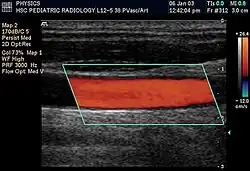

Doppler ultrasonography is used to study blood flow and muscle motion. The different detected speeds are represented in color for ease of interpretation, for example leaky heart valves: the leak shows up as a flash of unique color. Colors may alternatively be used to represent the amplitudes of the received echoes.

Doppler ultrasonography employs the Doppler effect to assess whether structures (usually blood)[58][61] are moving towards or away from the probe, and their relative velocity. By calculating the frequency shift of a particular sample volume, flow in an artery or a jet of blood flow over a heart valve, its speed and direction can be determined and visualized, as an example. Color Doppler is the measurement of velocity by color scale. Color Doppler images are generally combined with gray scale (B-mode) images to display duplex ultrasonography images.[62] Uses include: